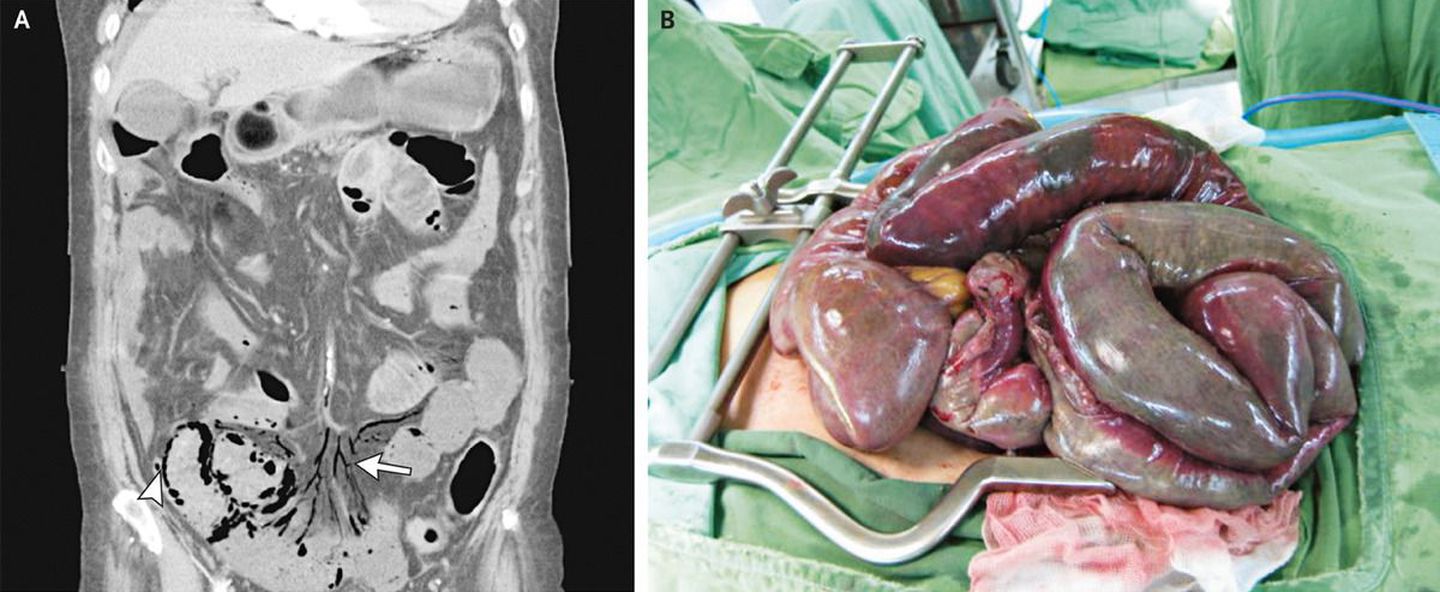

A 75-year-old woman with chronic atrial fibrillation presented to the hospital with a 2-day history of colicky abdominal pain. The physical examination revealed hypoactive bowel sounds and diffuse abdominal tenderness. Laboratory tests showed a white-cell count of 19,400 per cubic millimeter with 92% neutrophils, a blood urea nitrogen level of 42 mg per deciliter (15 mmol per liter), and a serum creatinine level of 3.0 mg per deciliter (267 ΞΌmol per liter). Abdominal computed tomography with contrast material showed occlusion of the main trunk of the superior mesenteric artery with mesenteric venous gas (Panel A, reconstructed coronal image, arrow) and pneumatosis intestinalis (arrowhead). Laparotomy revealed ischemic changes with congestion and transluminal necrosis of the small bowel (Panel B) and ascending colon. The superior mesenteric artery is susceptible to embolic occlusion because of its large caliber and narrow take-off angle from the aorta. Although surgical resection of the necrotic bowel is the treatment of choice, the patient and her family opted for conservative treatment. The patient died 3 days later.